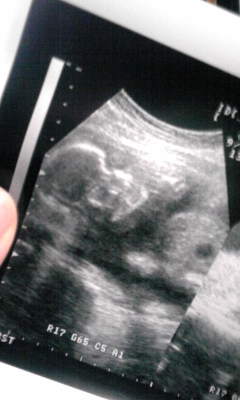

初公開赤ちゃんのエコー写真です!!(*´∀`人)

実は前回病院に行った時も1枚もらったんですけど、まだ全然形わかんなくて何か怖くて;;UP出来ずにいたんですよ。(うっかり「気持ち悪い」って言っちゃった時に弟に「赤ちゃん聞いとるからそんなことゆったらアカン」て怒られて反省したのもイイ思い出になりそうです(笑)

でも今回恐る恐る見てみると、なんだか人の形してるのが分かってきましたよ!分かりますか??まだ骨の部分しか写らないそうです。UPしたのは頭なんですけど・・ななめ上向いてて白い部分が骨で、目の部分が黒く抜けてるんですけど・・やっぱ分かりにくいですね(´・ω・`)まだまだ「カワイイ!!」とは言えないけど(笑)父と意外にも妹が「かわいい」て言ってくれました~☆よかったねタコスケちゃん

(仮)ぇホントよく動く子で、この写真を撮る時にも動いて逃げちゃって大変でした(^^;)それと今回は性別が分かるかもしれない!と思って期待してたんですが、まだイマイチ分かりませんでした↓↓早く名前考えたいんですけどねえ・・だから今はいつか飼う予定の猫の名前「タコスケ」て呼んだりしてます(笑)ちなみに私は両親の希望とか聞いてから考えたいと思ってます(´∀`)だって初孫になるんですから~